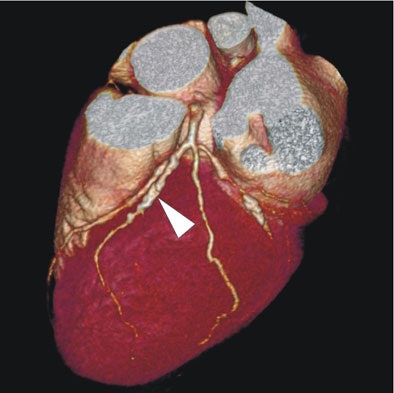

| In a 64-year-old man presenting with chest pain, 3D and multiplanar reconstructions of coronary CTA images show a significant stenosis in the first diagonal branch of the left anterior descending (LAD) artery and a 70% stenosis in the mid right circumflex artery (RCA) (arrows). All images courtesy of Dr. Balázs Ruzsics, Ph.D., and Dr. U. Joseph Schoepf. |